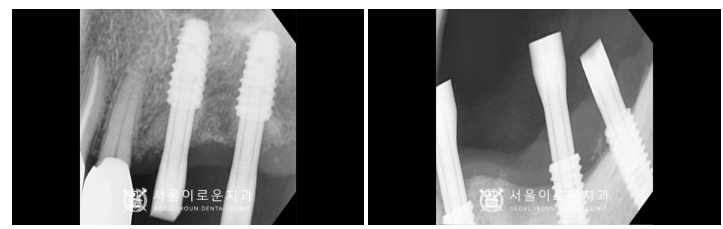

임플란트 식립 후

임플란트와 치조골이 단단하게 결합되기를

3~4개월 정도 충분히 기다린 후

osstell beacon이라는

골 유착을 확인할 수 있는 장비를 이용하여

isq(골유착정도) 측정하여

안정 값을 확인한 뒤

보철물 제작 인상채득을 진행했습니다.